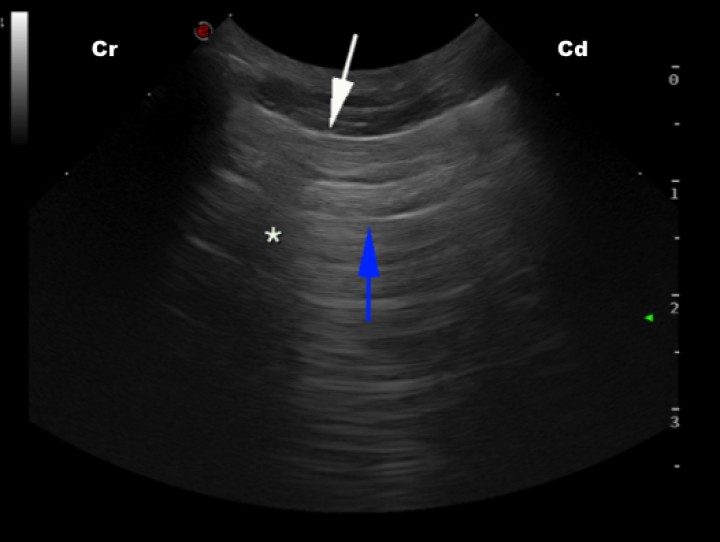

En cuanto a los hallazgos de la T-FAST, en condiciones normales en ambas proyecciones DC debemos observar las denominadas líneas A, aquellas líneas horizontales hiperecoicas paralelas a la interfase pleura-pulmón o línea PP, resultantes de la reverberación del aire contenido en el borde pulmonar (Fig. 4).[ Boysen S, Lisciandro G: The Use of ultrasound for dogs and cats in the emergency room. AFAST and TFAST. Vet Clin Small Anim 2013; 43: 773-797. [PubMed] ] Por el contrario, si visualizamos las líneas B, que son líneas hiperecoicas verticales fácilmente reconocibles, estaremos ante un pulmón con patología, ya que están presentes en el denominado pulmón húmedo o síndrome intersticial. Las líneas B se extienden desde la línea PP hasta el final de la pantalla, no se atenúan y oscilan como un péndulo con el movimiento respiratorio (Fig. 5).[ Lisciandro G: Abdominal and thoracic focused assessment with sonography for trauma, triage, and monitoring in small animals. J Vet Emerg Crit Care 2011; 21(2): 104-122. [PubMed] , Boysen S, Lisciandro G: The Use of ultrasound for dogs and cats in the emergency room. AFAST and TFAST. Vet Clin Small Anim 2013; 43: 773-797. [PubMed] , Andrea M, Walters A, O’Brien MA, Selmic LE, et al.: Evaluation of the agreement between focused assessment with sonography for trauma (AFAST/TFAST) and computed tomography in dogs and cats with recent trauma. J Vet Emerg Crit Care 2018: 1-7. [PubMed] ] Entre los principales diagnósticos diferenciales que se plantean una vez identificadas, cabe destacar el edema pulmonar (de origen cardiogénico o no), inflamación supurativa o contusión pulmonar en caso de pacientes traumatizados.[ Lisciandro G: Abdominal and thoracic focused assessment with sonography for trauma, triage, and monitoring in small animals. J Vet Emerg Crit Care 2011; 21(2): 104-122. [PubMed] , Boysen S, Lisciandro G: The Use of ultrasound for dogs and cats in the emergency room. AFAST and TFAST. Vet Clin Small Anim 2013; 43: 773-797. [PubMed] ]

<p>Imagen ecográfica de pulmón de un paciente sano en la que se observa la línea PP (interfase pleura-pulmón) como una fina línea hiperecoica (flecha blanca), así como líneas A hiperecoicas y paralelas entre sí (flecha azul) y la sombra acústica generada por una costilla (asterisco). Cr: craneal; Cd: caudal.</p>

Imagen ecográfica de pulmón de un paciente sano en la que se observa la línea PP (interfase pleura-pulmón) como una fina línea hiperecoica (flecha blanca), así como líneas A hiperecoicas y paralelas entre sí (flecha azul) y la sombra acústica generada por una costilla (asterisco). Cr: craneal; Cd: caudal.